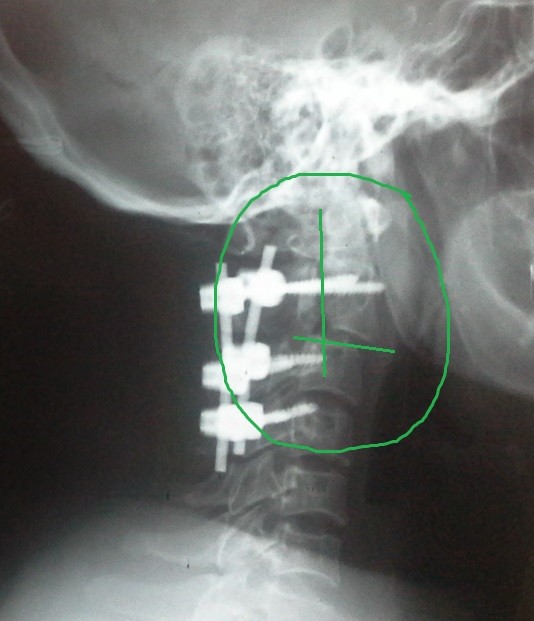

fracture of the second cervical vertebra with displacement between the second and third cervical